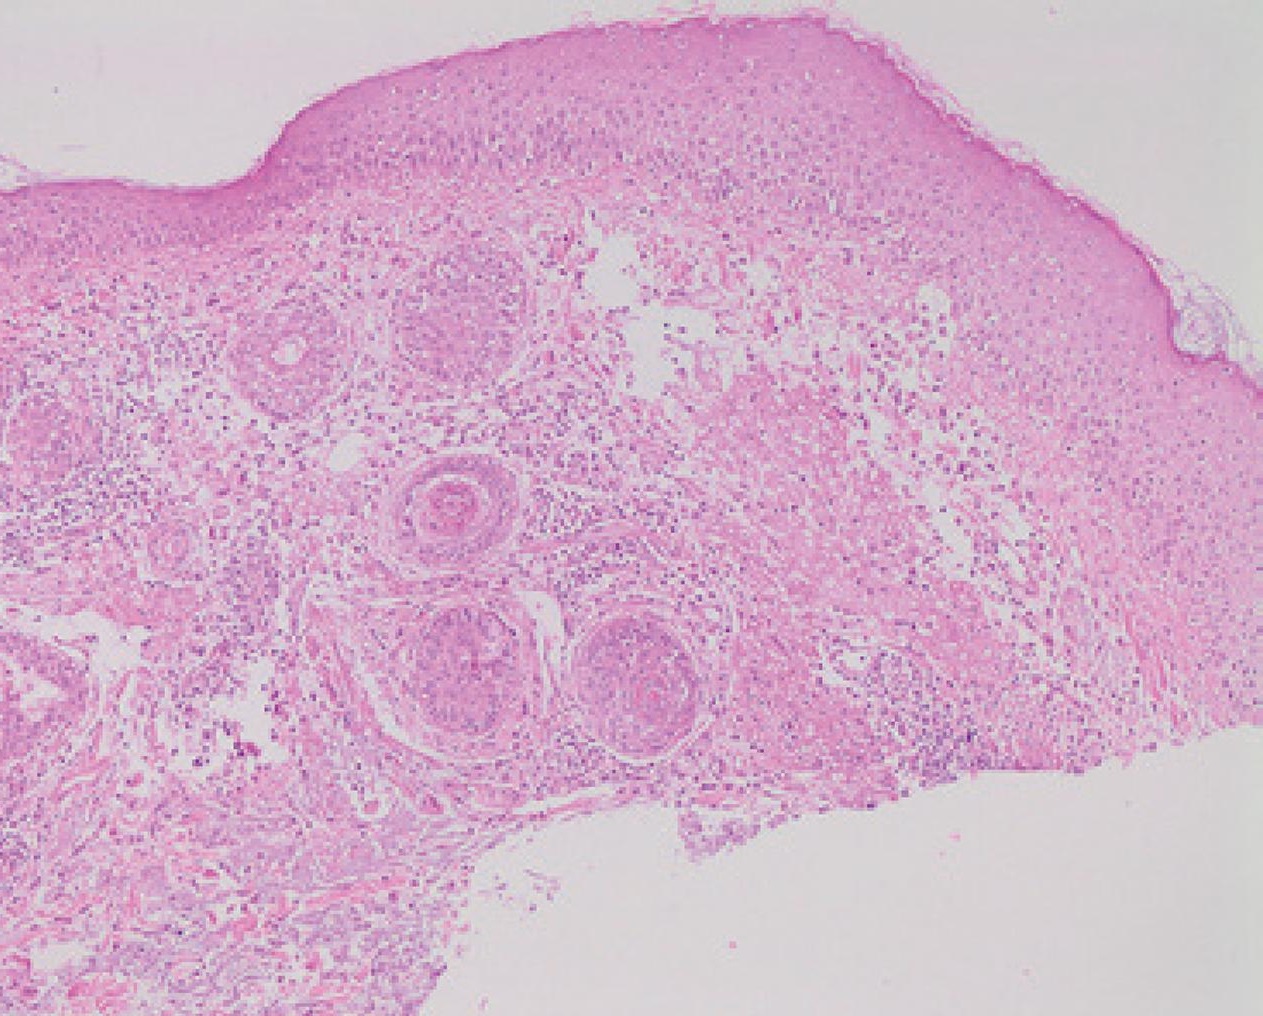

Description: Micrograph of rosacea. A skin biopsy showing rosacea as enlarged, dilated capillaries and venules located in the upper dermis, angulated telangiectasias, perivascular and perifollicular lymphocytic infiltration, and superficial dermal edema. Concurrently, there is also solar elastosis (H&E; 100×).

Title: Micrograph of rosacea